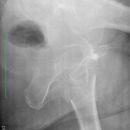

HüftTEP Luxation